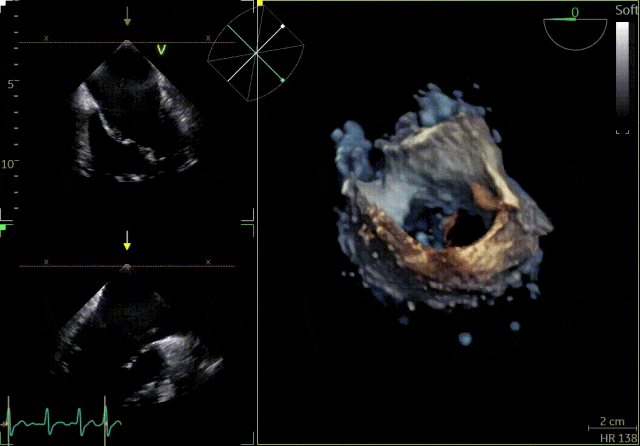

患者为41岁男性,心脏彩超提示:二尖瓣P2脱垂合并房性机制,左心扩大、瓣环扩张,反流主要来源于2区。反流宽度:20mm,2区瓣叶长度:2.2/1.3cm,AP径:43mm,瓣口面积:6.0cm²。

术前

X-plane 2区

X-plane 2区彩色

3D

3D彩色